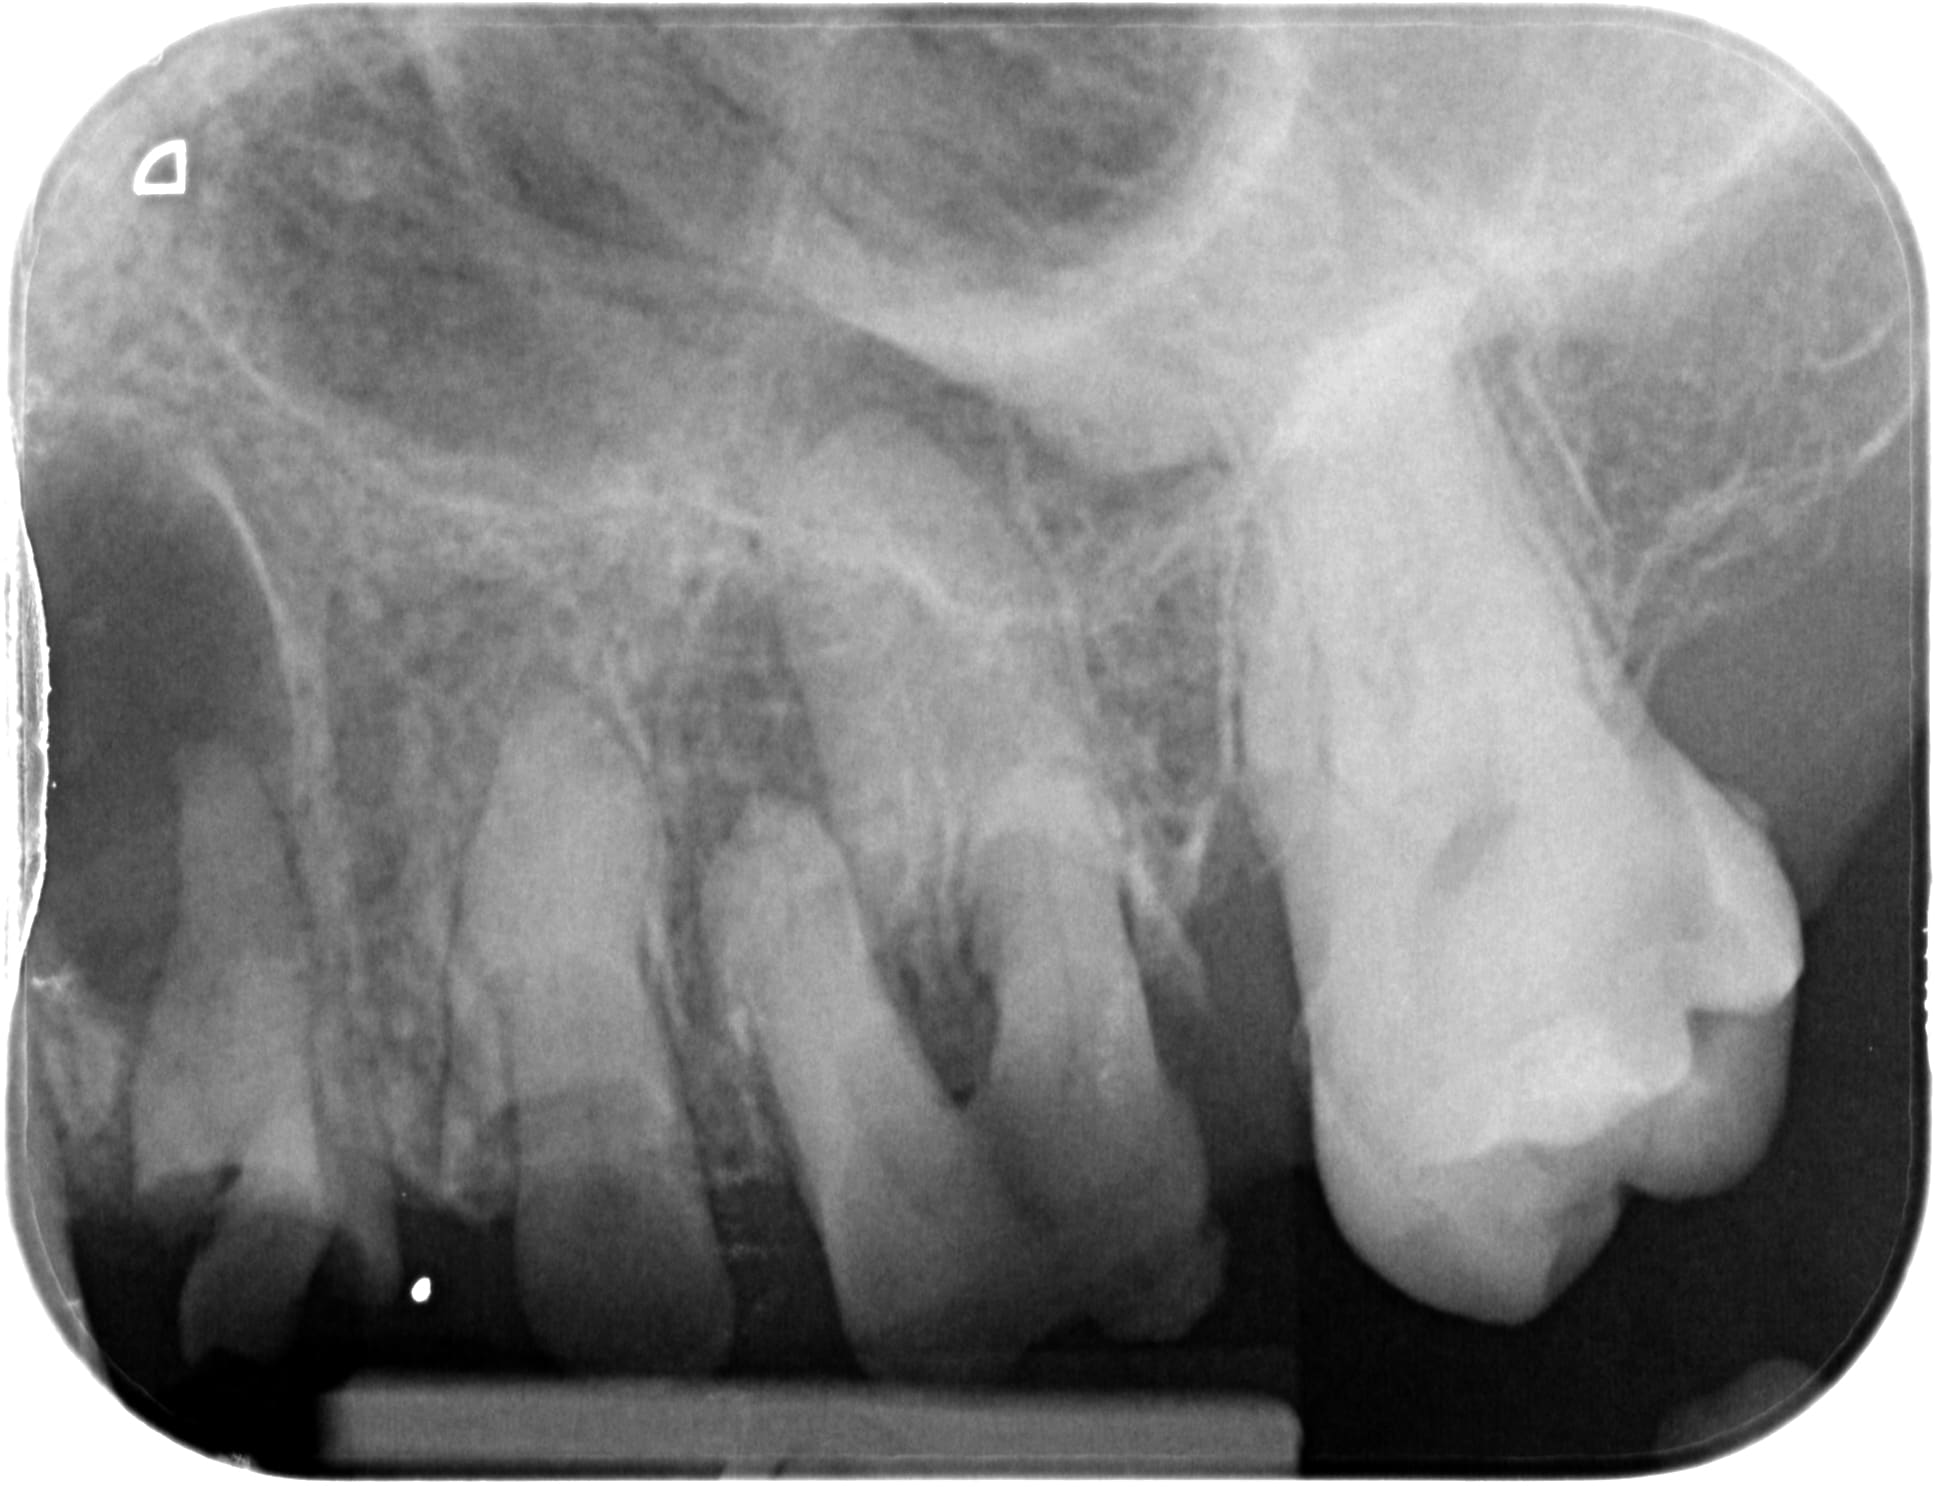

Des comme ça j'en 2 ou 3 par semaine (vu à l'instant ) ... Petite question : quel âge à ce patient ? Deuxième question à Carident et à quelques autres, quel est le montant de votre plan de traitement ? ( je ne demande pas le détail )(@ lardon , la 15 en métal , marqueur social ? ) .. troisième question : pensez vous que ce patient a la mutuelle adéquate à son état dentaire et enfin : pensez-vous que ce patient serait mieux pris en charge grâce au RAC 0 ? On va faire dans le concret de pas mal de cabinet dentaire ....

Pour l'age, c'est pas pour l'expulser, mais c'est impossible à dire par rapport à la radio. Au delà de 18 ans, c'est certain, tu ne sera pas arrêté pour détournement de mineur.

Puisque tu en parles, ca doit être la trentaine. Il a eut différentes extractions réalisées au cour du temps et à abandonné déjà les soins en cours de route.

C'est bien pour cela que c'est impossible de parler de devis et de tarifs, puisque quelque soit le devis, les probabilités d'arriver au bout du plan de traitement sont faible et il abandonnera bien avant les prothèses sur des soins opposables ce qui montre que le tarif et les remboursements ne sont pas en cause.

Age 19 Ans ! , et bien sûr qu'il ira au bout du traitement s' il peut financièrement ! Il est motivé , c'est un jeune homme "bien" . sérieux , il est à l'heure , n'est pas peureux .. bref , ce genre de patient où tu sais pertinemment que ce qui va coincer c'est l'argent . Barba , il existe des patients non serieux à tous les niveaux de la société et quand c'est un cadre , là , on pense qu'il n'a pas le temps . Alors , on fait quoi pour ce jeune , on le prend en charge ( nous la société ...) ? on lui dit que c'est trop tard ? t'avais qu'à te brosser les dents ? ( vous avez remarqué qu'il a eu déjà de nombreux soins ) . Et, s'il vous plait, gardez pour vous vos généralisations à 2 balles ! ( barba , tu me suis ? ) . Ah ouais aussi , je ne lui ai pas mis un devis sous le nez avant de commencer à le soigner .. évidemment !

Je précise aussi , ce patient n'est pas venu parce qu'il avait mal .... étrange , non ?